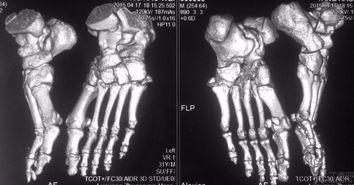

首先,得先弄明白什么是前臂脱臼。简单来说,就是你的前臂关节突然脱离了原来的位置,就像一个精密的机械突然出了故障。这种情况在日常生活中并不少见,比如摔倒、扭伤等。

那么,如何才能把脱臼的前臂复位呢?这就需要我们掌握一些专业的手法。下面,就让我带你一步步来学习这个神奇的复位法。